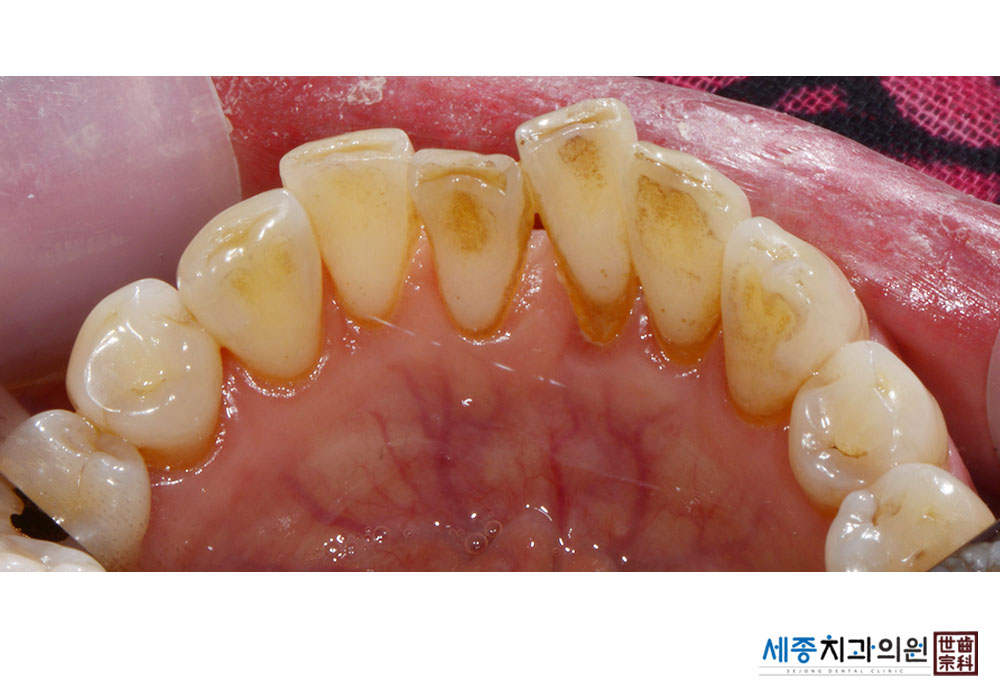

[스케일링] 치주질환 예방 스케일링

치료전 : 2022-04-04

치료후 : 2022-04-04

가글마취&저주파 스켈러를 사용한 스케일링